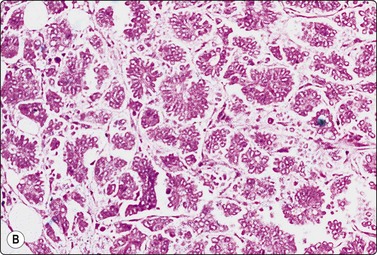

Fig. 7.2 Non-neoplastic glandular breast tissue and low-grade duct carcinoma

Low-power view; (A) Bimodal population of epithelial sheets and single bipolar nuclei of non-neoplastic glandular breast tissue; (B) Single population of epithelial cells in low-grade carcinoma (MGG, LP).

image image

Fig. 7.3 Non-neoplastic glandular breast tissue and low-grade duct carcinoma

High-power view, air-dried smears; (A) Non-neoplastic glandular breast tissue; (B) Low-grade duct carcinoma. Note single bipolar nuclei in A, and absence of bipolar nuclei, relatively mild nuclear atypia and some loss of cohesion of malignant cells in B (MGG, HP).

Fig. 7.4 Non-neoplastic glandular breast tissue and low-grade duct carcinoma

High-power view, Pap-stained smears; (A) Bimodal population in smear from non-neoplastic breast; (B) Single and clustered cells in low-grade carcinoma; some single cells probably stromal (Pap, HP).

A comparison between the basic benign pattern (non-neoplastic glandular tissue) and the most common malignant pattern (low-grade carcinoma of no special type) in FNB of breast lesions is given in Table 7.2 (Figs 7.2-7.4).

Table 7.2 Comparison of the benign pattern and low-grade carcinoma in FNB smears

Non-neoplastic breast tissue (Figs 7.2A, 7.3A and 7.4A) Low-grade carcinoma NOS (Figs 7.2B, 7.3B and 7.4B)

1. Overall low cell yield 1. Variable but higher cell yield

2. Sheets and aggregates of cohesive, small, uniform cells 2. Irregular clusters of less cohesive, small, mildly irregular cells

3. Small rounded nuclei, bland chromatin, some overlapping 3. Slightly larger and darker nuclei, relatively bland chromatin

4. Myoepithelial cell nuclei among epithelial cells 4. Myoepithelial cell nuclei not seen

5. Variable numbers of single, bare, bipolar nuclei scattered in the background 5. Single cells, most with some cytoplasm, identical to those forming clusters; no bare bipolar nuclei